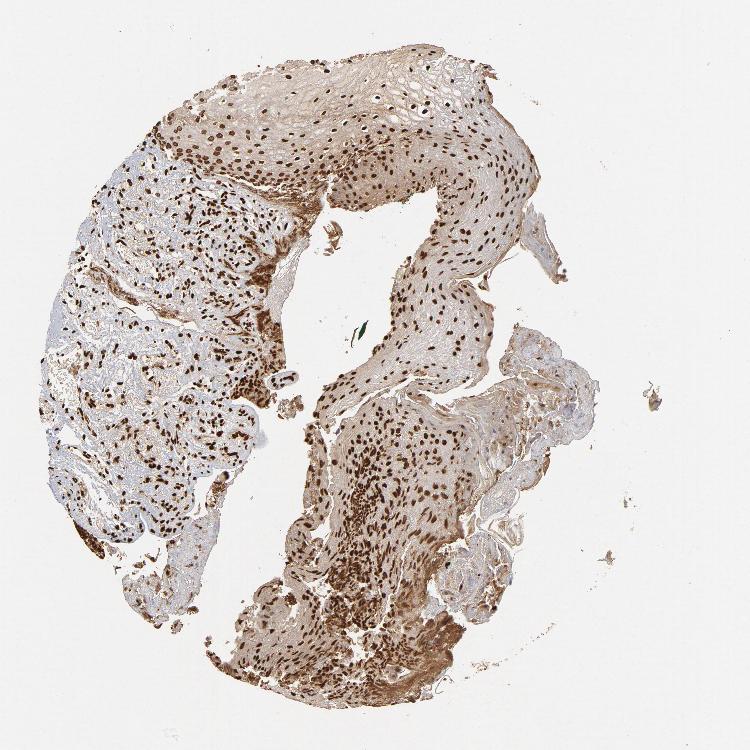

TISSUE PRIMARY DATA ORAL MUCOSA Show tissue menu

Oral mucosa

ORAL MUCOSA - Antibody stainingi

Antibody staining in the annotated cell types in the current human tissue is reported as not detected, low, medium, or high, based on conventional immunohistochemistry profiling in selected tissues. This score is based on the combination of the staining intensity and fraction of stained cells.

Each image is clickable and will lead to virtual microscopy that enables deeper exploration of all samples and also displays staining intensity scores, fraction scores and subcellular localization as well as patient and tissue information for each sample.

Antibody HPA006660Antibody CAB004022

Squamous epithelial cells HighHigh